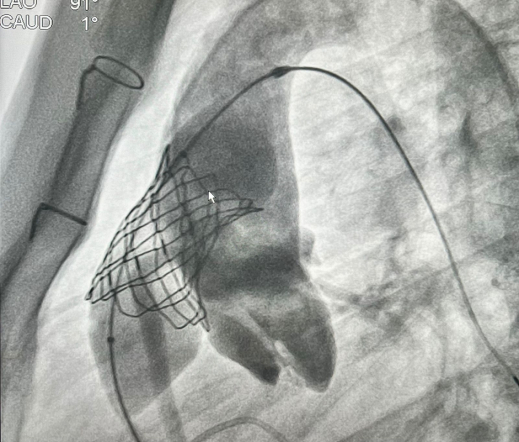

У пациента из Луганской Народной Республики просвет ранее имплантированного кондуита составлял 1,5 сантиметра, поэтому рентгенхирурги на первом этапе расширили его методом баллонной дилатации. При этом был риск разрыва сосуда, поэтому, чтобы избежать возможных осложнений, медики сначала имплантировали стентграфт – металлический каркас, покрытый герметичным полимером. Просвет кондуита удалось расширить до необходимого диаметра. Затем через бедренную вену хирурги доставили к сердцу искусственный биологический клапан лёгочной артерии Myval индийского производства.

Сложную операцию провела команда врачей Педиатрического университета - рентгенэндоваскулярные хирурги Михаил Комиссаров, Владимир Приворотский и Иван Алешин. Неоценимую помощь медикам СПбГПМУ оказал заведующий отделением рентгенэндоваскулярных методов диагностики и лечения Городской многопрофильной больницы №2 Евгений Шлойдо.